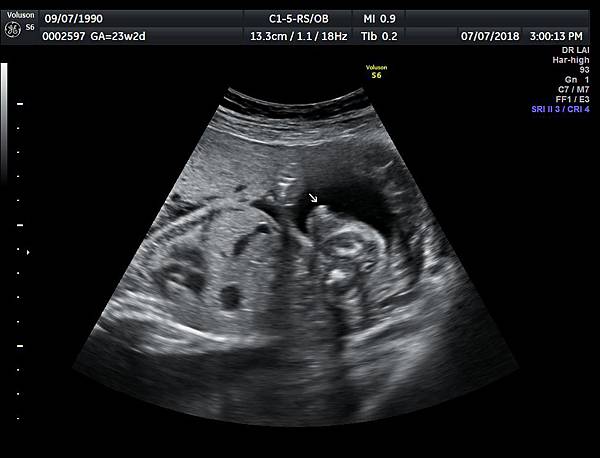

今天下午一位28歲第一胎的孕婦來診所做超音波檢查,之前他們一直認為懷的是女兒(檢查前資料顯示胎兒是女生);今天我的診斷胎兒是男生,但是懷疑有尿道下裂的問題(附圖 1~4),我的建議是抽羊水做染色體基因檢查,除了確定性別之外,也可以排除是否合併基因異常。

診斷尿道下裂常用的鬱金香sign(tulip sign)(附圖 10.11.),它的特徵就是龜頭陷入陰囊中間,胎兒如果是男生,一定要看到龜頭離開陰囊,這樣就沒有問題,每次遇到尿道下裂的個案時,我都會有一個感觸,男生如果能站著尿尿都要很感恩。